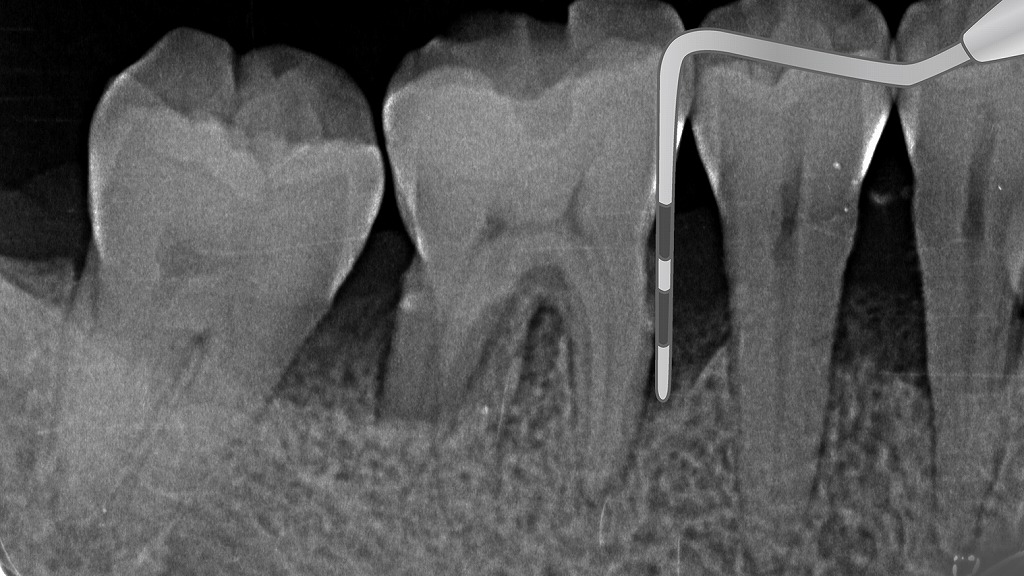

プロービングで分かる歯周病の進行度:重度と健康な歯の明確な違い

〈解説-深い歯周ポケットが確認できる重度歯周病の状態〉

プローブを挿入すると、根の深い位置までスッと入ってしまい、明らかに深い歯周ポケットが形成されています。

X線上でも、歯根周囲の骨が大きく吸収されており、水平的・垂直的な骨欠損が認められます。

これは歯周病が進行し、歯を支える骨が減っている典型的な所見です。

ポケットが深いほど細菌が停滞しやすく、動揺・腫れ・出血・口臭などのリスクが高まります。